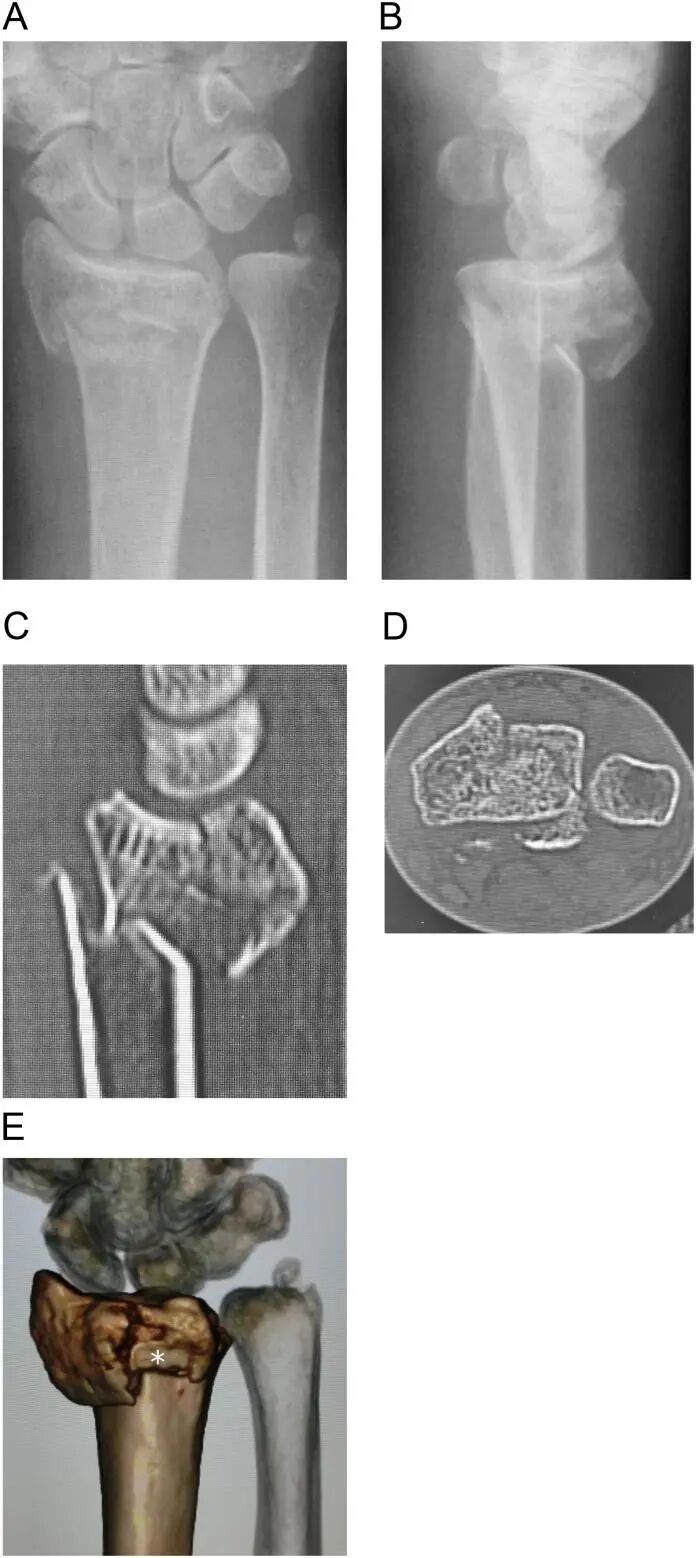

图1:术前影像显示粉碎性关节内桡骨远端骨折。A和B:术前X光片;C和D:计算机断层扫描图像的矢状和轴向视图;E:三维计算机断层扫描图像。背内侧月骨小面碎片和背顶碎片(白色星号)可见。 - Dorsal Tangential View(背侧切线位): 如前所述,这是一个特殊的放射学视图,旨在评估螺钉尖端与桡骨背侧皮质之间的距离。在术前规划时,如果怀疑存在背侧骨折块或需要双皮质固定,可尝试获取此视图,以初步评估螺钉突出的潜在风险。

病例为一名67岁的女性,诊断为关节内不稳定的桡骨远端骨折,右侧有一个背内侧骨折(图1 A-E)。术中,我们钻穿了背侧皮质,并选择了一个足够长的螺钉来固定不稳定的背内侧碎片。-